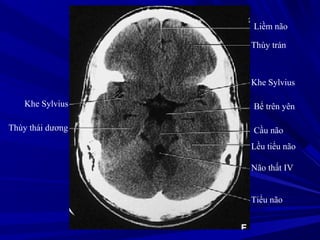

Liềm não

Thùy trán

Khe Sylvius

Bể trên yên

Cầu não

Lều tiểu não

Não thất IV

Tiểu não

Thùy thái dương